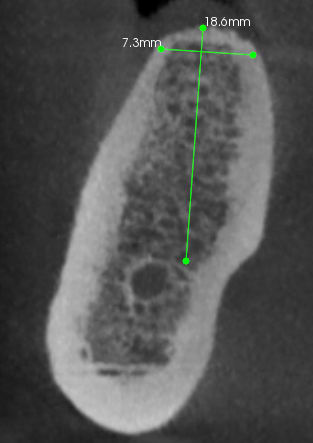

Bin Ă©coute y aucune recherche Ă  faire. j'ai de l'os en V de 13. Cet Implant est lĂ©gĂšrement vestibulĂ© et donc je vais corriger ça avec un pilier CFAO. J'ai fait mon expansion dans l'axe de la crĂȘte alors qu'il aurait fallu lĂ©gĂšrement dĂ©placer plus En interne l'implant.

Moi y a pas de soucis je suis tout à fait d'accord avec toi l'implant canine est vestibulé et un peu éloigné de la latérale. J'en suis pas fiÚre. Je dis juste que je vais corriger ça avec la prothÚse. Y a pas mort d'homme